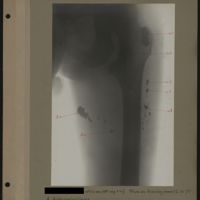

0012 - Page 8 - [Radiographie de la hanche et du fémur]0012 - Page 8 - [Radiographie de la hanche et du fémur]

0038 - Page 34 - [Radiographie du fémur]0038 - Page 34 - [Radiographie du fémur]

0053 - Page 49 - [Radiographie du fémur]0053 - Page 49 - [Radiographie du fémur]

0055 - Page 51 - [Radiographie du fémur]0055 - Page 51 - [Radiographie du fémur]

0056 - Page 52 - [Radiographie du fémur?]0056 - Page 52 - [Radiographie du fémur?]

0057 - Page 53 - [Radiographie du fémur]0057 - Page 53 - [Radiographie du fémur]

0085 - Page 81 - [Radiographie de la hanche et du fémur]0085 - Page 81 - [Radiographie de la hanche et du fémur]

0087 - Page 83 - [Radiographies du fémur]0087 - Page 83 - [Radiographies du fémur]

0090 - Page 86 - [Radiographie du fémur]0090 - Page 86 - [Radiographie du fémur]

0093 - Page 89 - [Radiographies du fémur]0093 - Page 89 - [Radiographies du fémur]

0099 - Page 95 - [Radiographies du fémur]0099 - Page 95 - [Radiographies du fémur]